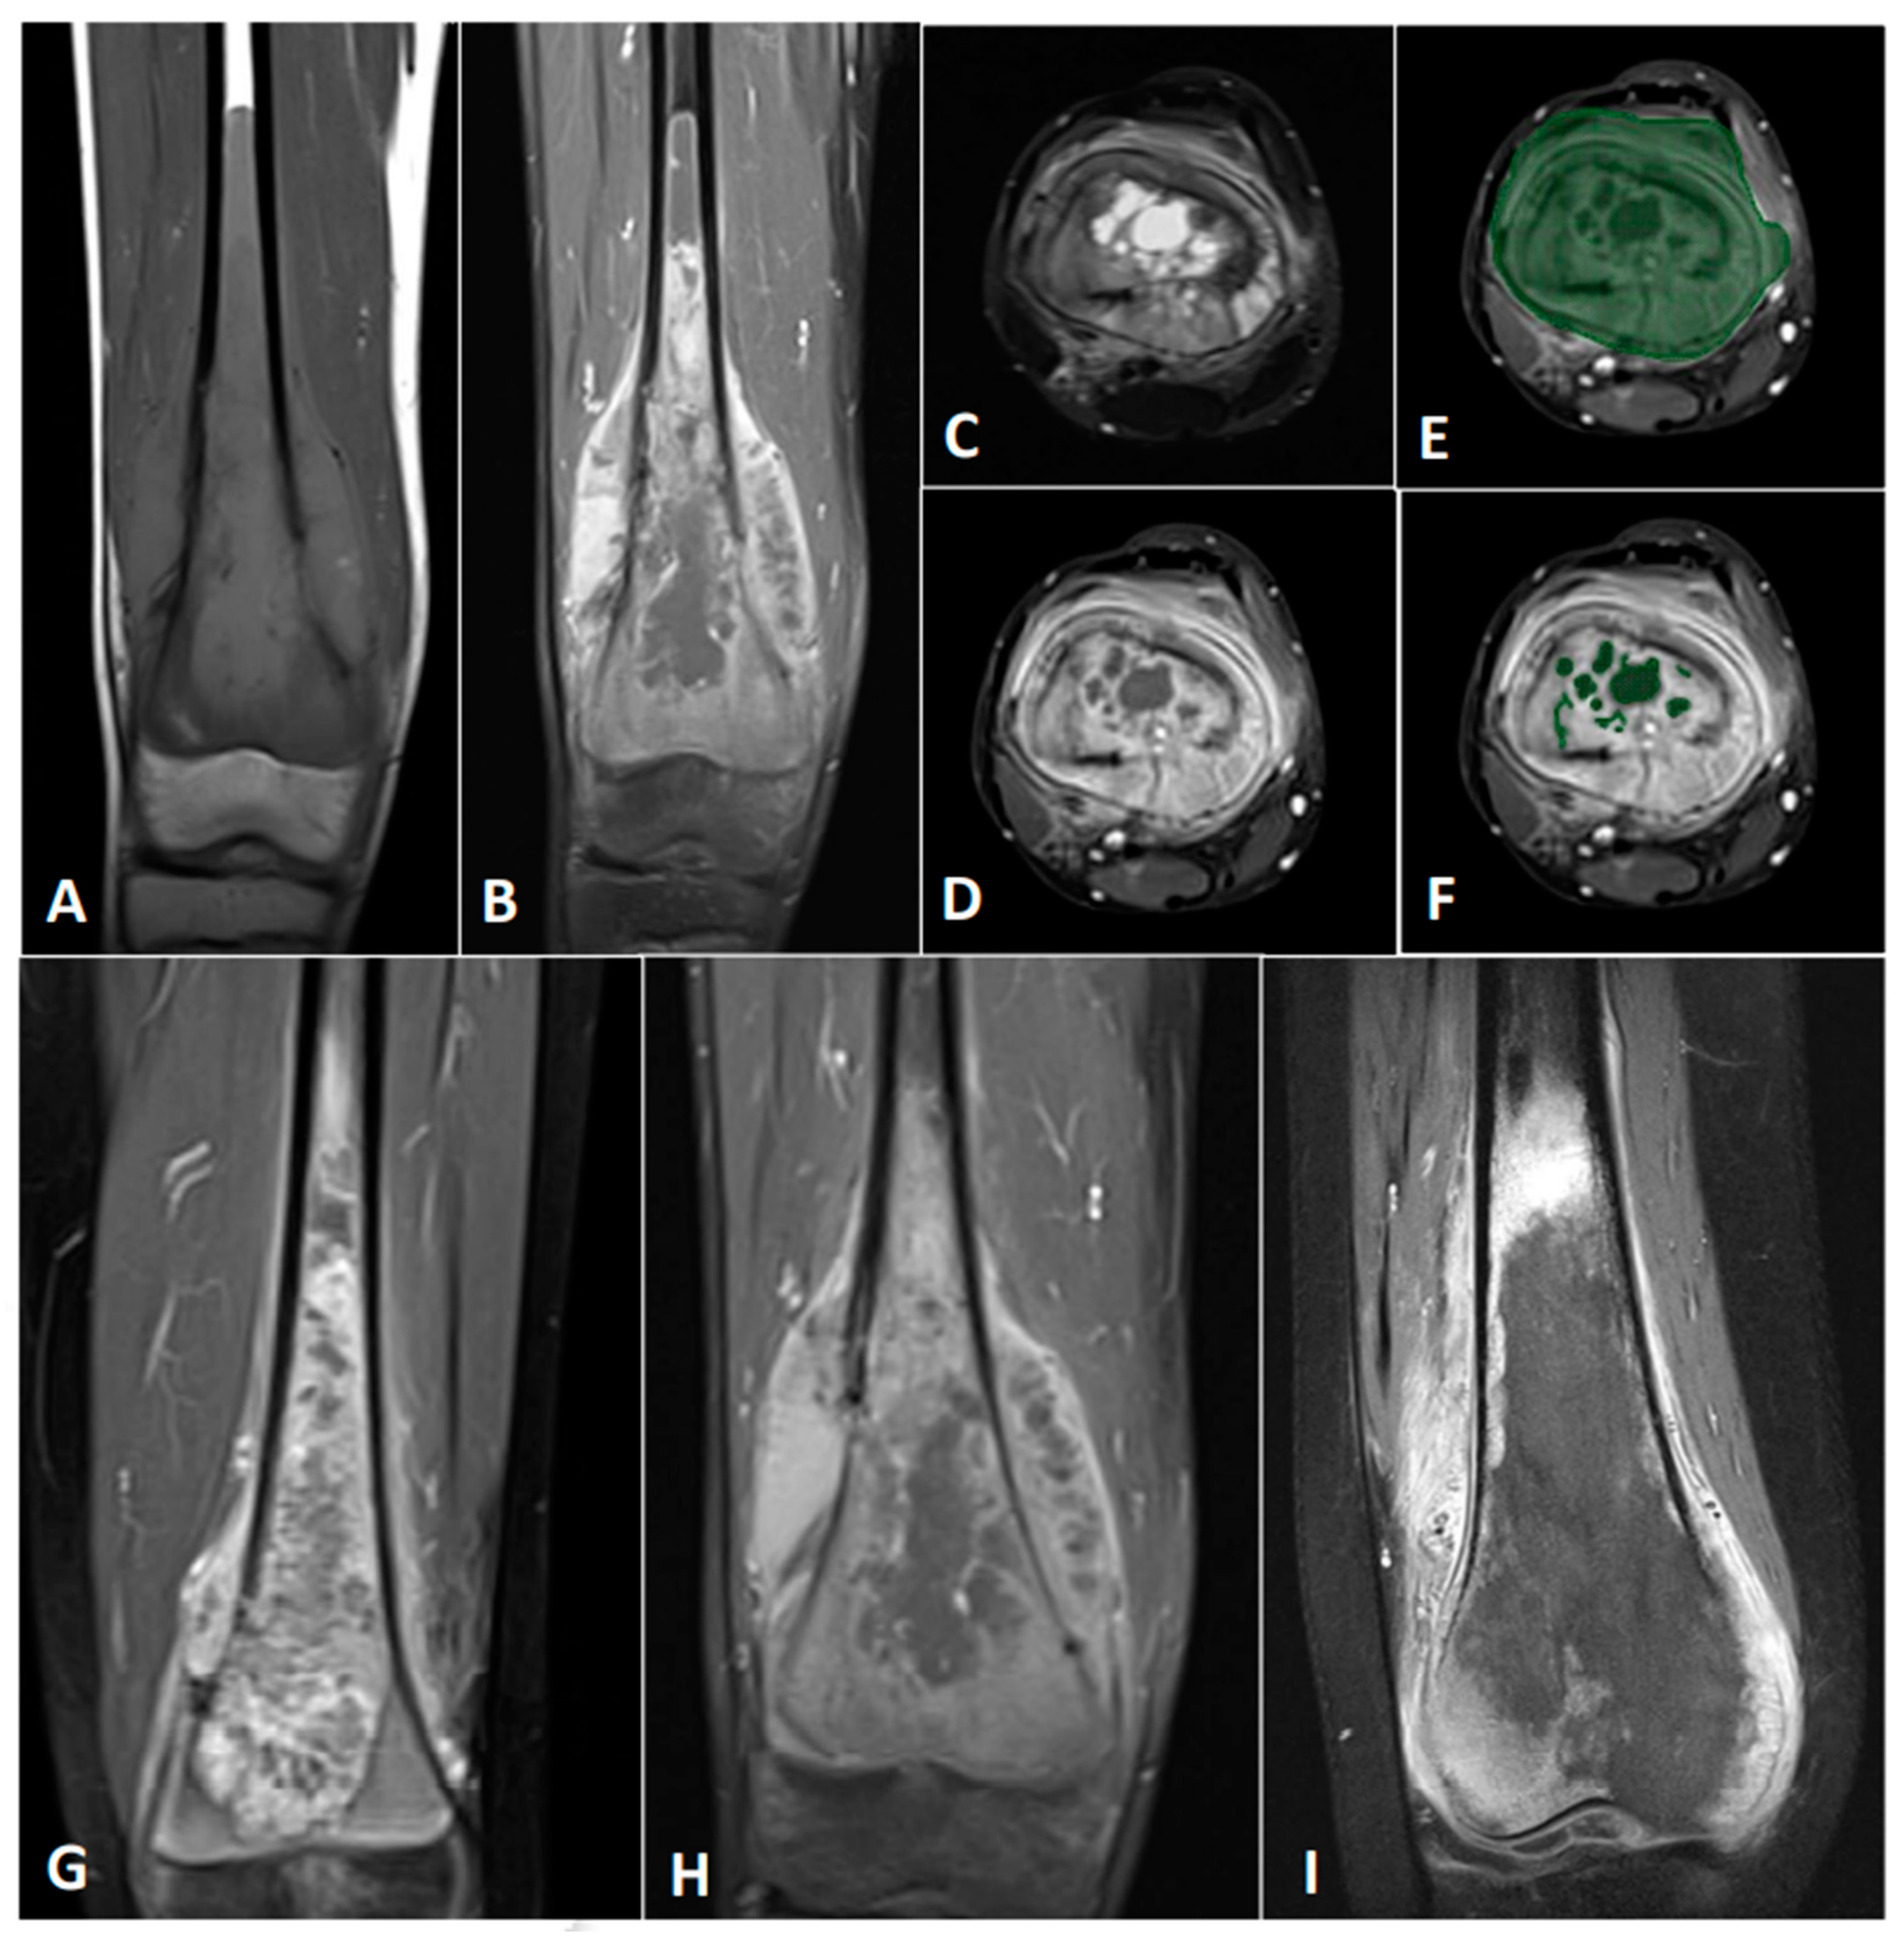

2.2. MRI and Its Processing